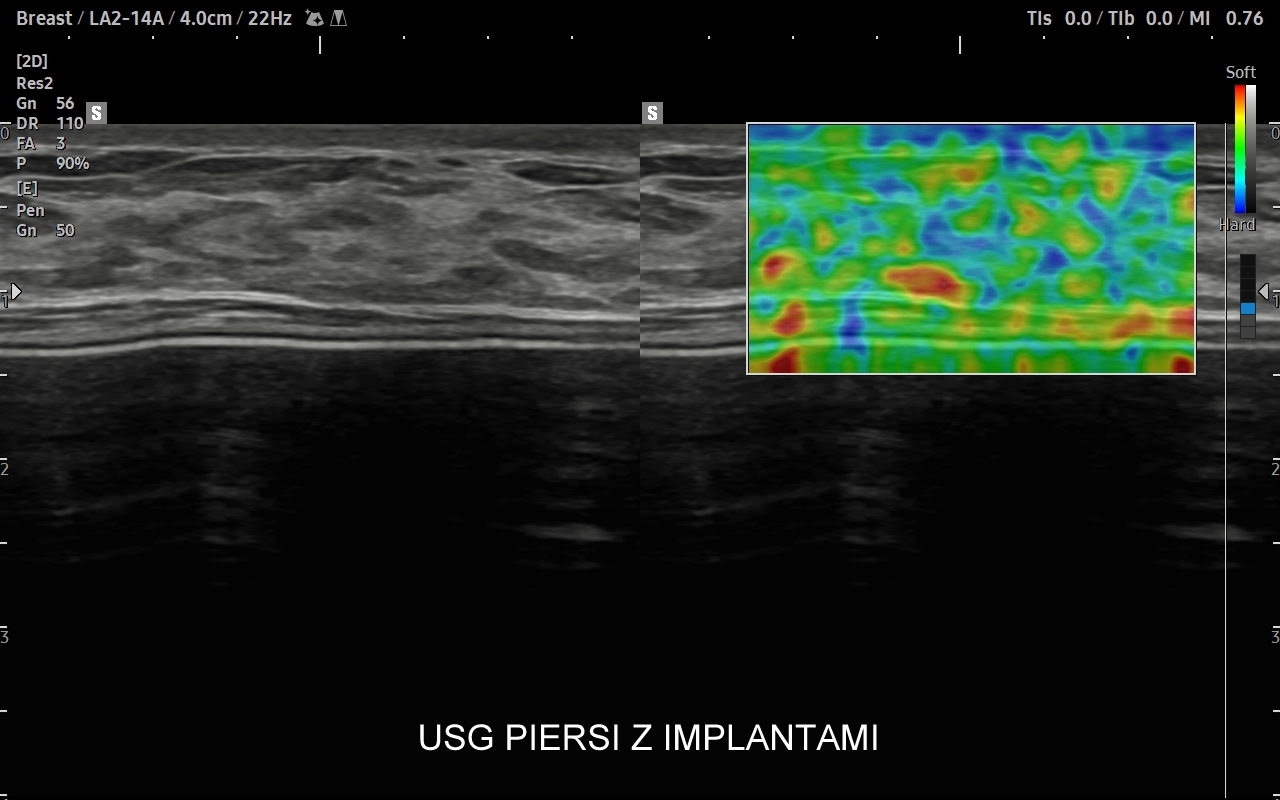

USG piersi z implantami

Badanie USG piersi z implantami jest szczególną procedurą diagnostyczną. Przeprowadza się ze wskazań wcześniej opisanych, jak w przypadku piersi bez implantów, ale także w schorzeniach ściśle związanych z implantem. Przykładami są powikłania chirurgiczne takie jak przemieszczenie się implantu, krwiak, ropne zapalenie tkanek wokół implantu, jego pęknięcie, a także wystąpienie chłoniaka BIA-ALCL (ang. breast implant associated anaplastic large cell lymphoma) jako odległego powikłania wszczepienia implantu piersi.